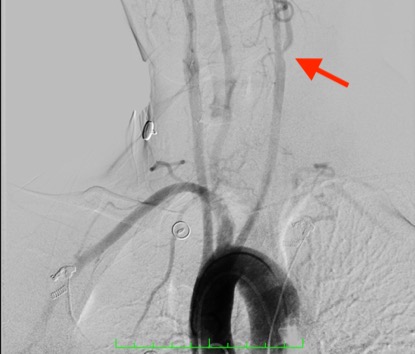

该例患者为49岁男性,头晕 2月余,外院颈动脉超声提示左侧颈内动脉重度狭窄,遂专程赴我院神经内科就诊,拟行脑血管造影评估狭窄程度,必要时行介入治疗。该患者住院后顺利完成相关术前评估并进行了脑血管造影检查,但造影结果却令人吃惊,该患者主动脉弓为罕见的右位主动脉弓伴左锁骨下动脉起始部缺如(图1)。这种主动脉弓型属于先天变异,非常罕见,极大的增加了手术难度。同时,患者造影证实左侧颈内动脉起始部重度狭窄,狭窄率>70%(图1红色箭头),医疗组讨论后一致认为从脑血管病二级预防角度有行支架植入的指征。充分向患者及家属告知了手术难度极大及相应的风险,患者及家属商议后实施手术。

图1患者主动脉弓呈罕见的右位III型主动脉弓,红色箭头指左侧颈内动脉起始部重度狭窄